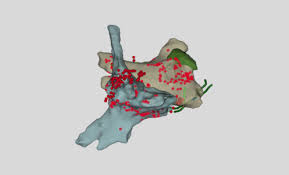

Elektrophysiologische untersuchung mit ablation. Mit einer elektrophysiologischen Untersuchung EPU wird zunächst festgelegt wo genau im Erregungsleitungssystem die Ablation stattfinden soll. Die Verödung der Lungenvenen Pulmonalvenenisolation kommt bei der häufigsten Herzrhythmusstörung dem Vorhofflimmern zum Einsatz. Die elektrophysiologische Untersuchung mit gleichzeitiger Ablation kann zeitaufwendig sein.

Sie dient meist der genauen Abklärung von Herzrhythmusstörungen die zum Beispiel in einem vorhergehenden EKG festgestellt oder durch Symptome wie Herzrasen auffällig wurden. Durch die Ablation werden die Herzmuskelzellen die für die Rhythmusstörung verantwortlich sind verödet also dauerhaft zerstört. Katheterablation - modulation Im Rahmen der elektrophysiologischen Untersuchung kann bei bestimmten.

Mit dem Verfahren der Ablation können bestimmte Herzrhythmusstörungen bei denen. Das funktionelle Abschalten elektrisch aktiver Herzgewebeanteile. Den Möglichkeiten des Verfahrens stehen eine Reihe von relevanten Limitationen entgegen. Sie dient meist der genauen Abklärung von Herzrhythmusstörungen die zum Beispiel in einem vorhergehenden EKG festgestellt oder durch Symptome wie Herzrasen auffällig wurden. Die Verödung erfolgt durch spezielle Katheter im Herzen mit hochfrequentem Wechselstrom oder. Elektrophysiologische Untersuchung EPU Katheterablation - modulation. Einer elektrophysiologischen Untersuchung die genaue Diagnose gesichert wurde.